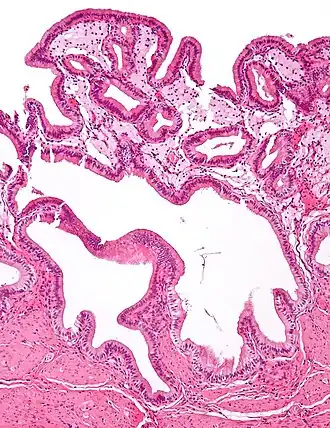

-

Micrograph of cholesterolosis of the gallbladder -